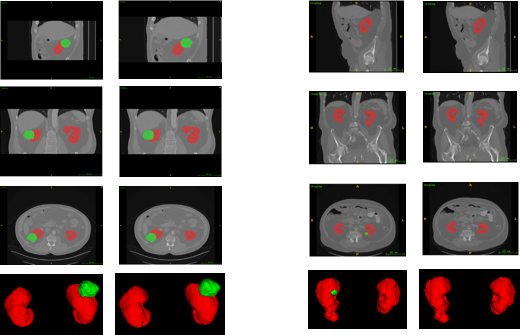

The samples of our segmentation outputs are shown in Fig.4. We observed both 2D slices from different views and 3D view to analyze the performance. Obviously, the kidney in CT images was segmented pretty well. The prediction was closely approximate the ground truth. However, some tumor was too small to get good Dice Coefficient, and also was difficult to find. Some cases with small tumor size would decrease the average Dice Coefficient drastically.